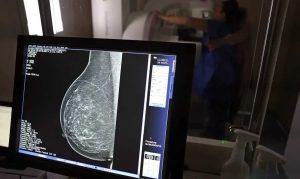

O Ministério da Saúde passou a recomendar o acesso a mamografia, via Sistema Único de Saúde (SUS), para mulheres de 40 a 49 anos – mesmo que não haja sinais ou sintomas de câncer de mama. De acordo com a pasta, a faixa etária concentra 23% dos casos da doença, e a detecção precoce aumenta as chances de cura.

Até então, a orientação era que o exame fosse feito a partir dos 50 anos.

A medida faz parte de um conjunto de ações anunciadas nesta terça-feira (23) voltado para a melhoria do diagnóstico e da assistência. A recomendação para mulheres a partir dos 40 anos é que o exame seja feito sob demanda, em decisão conjunta com o profissional de saúde.

As mamografias via SUS em pacientes com menos de 50 anos, de acordo com a pasta, representam 30% do total, o equivalente a mais de 1 milhão apenas no ano de 2024.